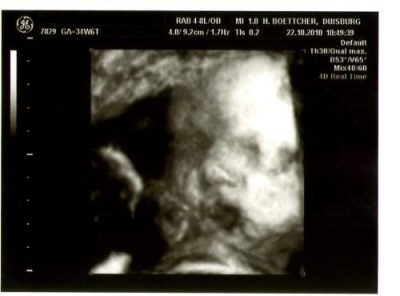

@Liebe Maja76: Oh, Du hast auch ein total schönes Bild von Deinem Krümel bekommen